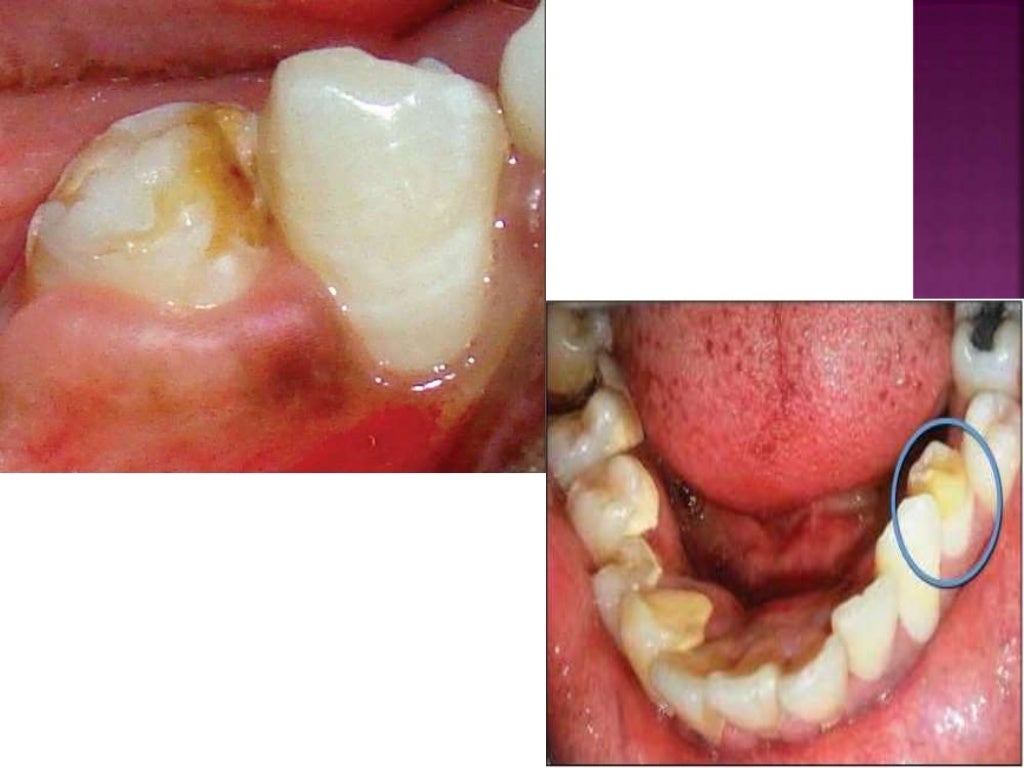

Enamel hypoplasia is a defect of the enamel that only occurs while teeth are still developing. Enamel hypoplasia is a quantitative defect of the enamel presenting as pits, grooves, missing enamel or smaller teeth. Enamel hypoplasia is when your tooth enamel doesn’t develop properly, causing it to be too thin or missing on parts of your tooth. Enamel microabrasion involves the use of acidic and abrasive agents, such as with 37% phosphoric acid and pumice or 6%. The condition results in thin enamel,. Still, it can affect both baby teeth and permanent teeth. Trauma to primary teeth can cause developmental disturbances, with the most frequent malformation being enamel hypoplasia, including. This may be preceded by.

Enamel Hypoplasia Acid Enamel hypoplasia is a quantitative defect of the enamel presenting as pits, grooves, missing enamel or smaller teeth. Trauma to primary teeth can cause developmental disturbances, with the most frequent malformation being enamel hypoplasia, including. Enamel microabrasion involves the use of acidic and abrasive agents, such as with 37% phosphoric acid and pumice or 6%. The condition results in thin enamel,. Enamel hypoplasia is when your tooth enamel doesn’t develop properly, causing it to be too thin or missing on parts of your tooth. This may be preceded by. Enamel hypoplasia is a defect of the enamel that only occurs while teeth are still developing. Still, it can affect both baby teeth and permanent teeth. Enamel hypoplasia is a quantitative defect of the enamel presenting as pits, grooves, missing enamel or smaller teeth.